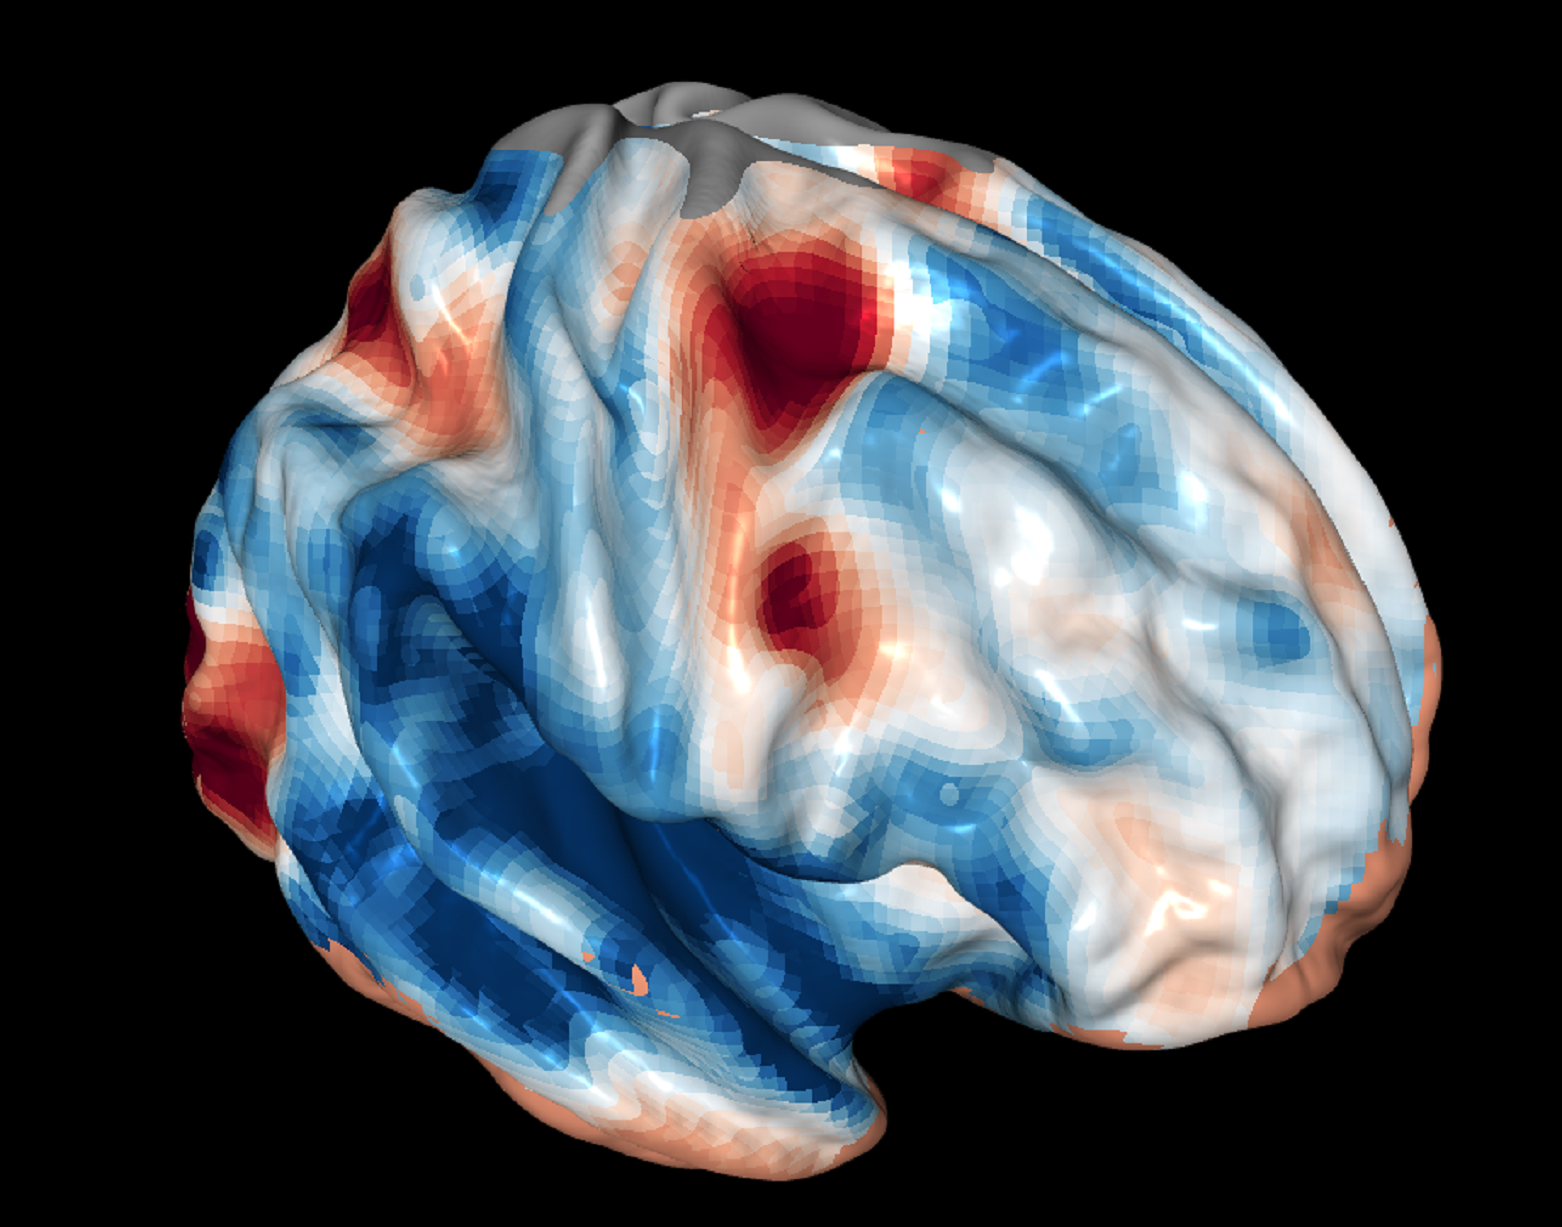

Imagen del cerebro de un escáner de resonancia magnética funcional durante pruebas del papel de la corteza frontal en la visión. Fuente: GA Tech.

En los experimentos, durante una exploración de resonancia magnética funcional, diferentes partes de la corteza frontal de los participantes se iluminaron, correspondientes a cada función de la visión.

La parte posterior de la corteza frontal se activaba durante la selección; su sección media lo hacía durante la combinación, y la parte delantera o anterior, durante la evaluación.

Esa es la forma en que los investigadores llegaron a una especie de mapa de la visión de la corteza frontal. "Es un mapa rudimentario", reconoce Rahnev. "Uno muy simple que sólo dice: "Esta es la parte de atrás. Esta la del medio. Esta es la parte delantera."

En los experimentos, durante una exploración de resonancia magnética funcional, diferentes partes de la corteza frontal de los participantes se iluminaron, correspondientes a cada función de la visión.

La parte posterior de la corteza frontal se activaba durante la selección; su sección media lo hacía durante la combinación, y la parte delantera o anterior, durante la evaluación.

Esa es la forma en que los investigadores llegaron a una especie de mapa de la visión de la corteza frontal. "Es un mapa rudimentario", reconoce Rahnev. "Uno muy simple que sólo dice: "Esta es la parte de atrás. Esta la del medio. Esta es la parte delantera."